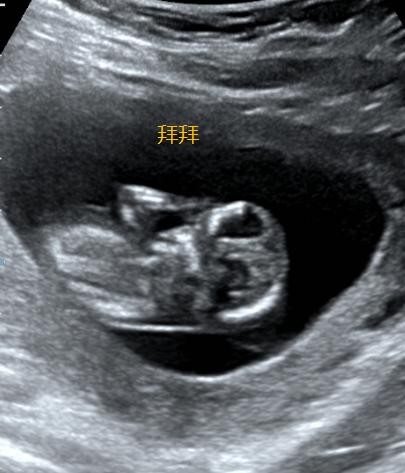

此时胎动已经开始活跃了,只是孕妈妈可能还感受不到。但在超声下却可以看到TA很活泼哟。

除了心跳,我们还能看见TA的整个身体雏形了。

手手脚脚都能看到一些。

甚至有时还能看见TA在肚子里舞蹈。

总之,这个时期胎儿已基本成型,在12周内的孕妈妈一定要记得去正规医院产科咨询咯,因为此时需要测量NT了。